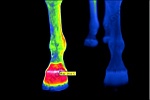

Biológiai alkalmazások

A termográfia biológiai alkalmazásai